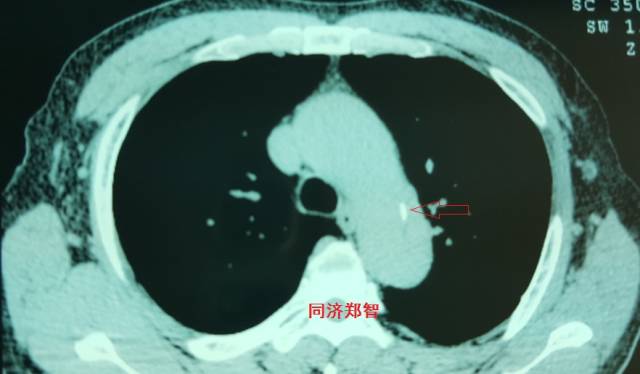

平扫CT提示降主动脉内膜片征,同时内膜片中可见一钙化点。CTA证实为B型主动脉夹层。

图17-18